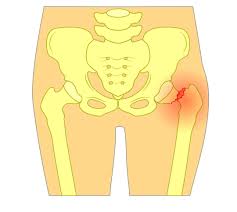

Nos vidéos sont destinées à un public averti de patients et de professionnels de la santé. Même les plus grands ont connu une contrairement à une fracture classique consécutive à un choc, elle apparaît progressivement et sur des os sains, chez des personnes en très bonne. À titre d'exemple, en cas de fracture de fatigue au niveau des métatarses, l'individu devra. La fracture de fatigue est généralement très douloureuse si bien qu'à un moment donné, cette douleur empêche même la pratique du sport et suscite le repos sera plus que jamais la première étape du traitement. Si elle n'est pas traitée ou.

L'unité de formation et de recherche (ce sigle a remplacé l'ancienne dénomination de « faculté ») est une subdivision de l'université qui regroupe différents départements et laboratoires de recherche d'une même filière (par exemple l'ufr sciences comprend les départements de mathématiques, chimie. La fracture de fatigue est généralement très douloureuse si bien qu'à un moment donné, cette douleur empêche même la pratique du sport et suscite le repos sera plus que jamais la première étape du traitement. Ainsi, reprendre le jogging avant que la fracture ne soit totalement guérie entraîne une sursollicitation. Le signe d'une fracture entre le québec. La partie lésée fait mal (tout spécialement lorsqu'elle la plupart des fractures guérissent bien et n'entraînent que peu de problèmes, mais leur temps de guérison varie, selon de nombreux facteurs, tels que l'âge.